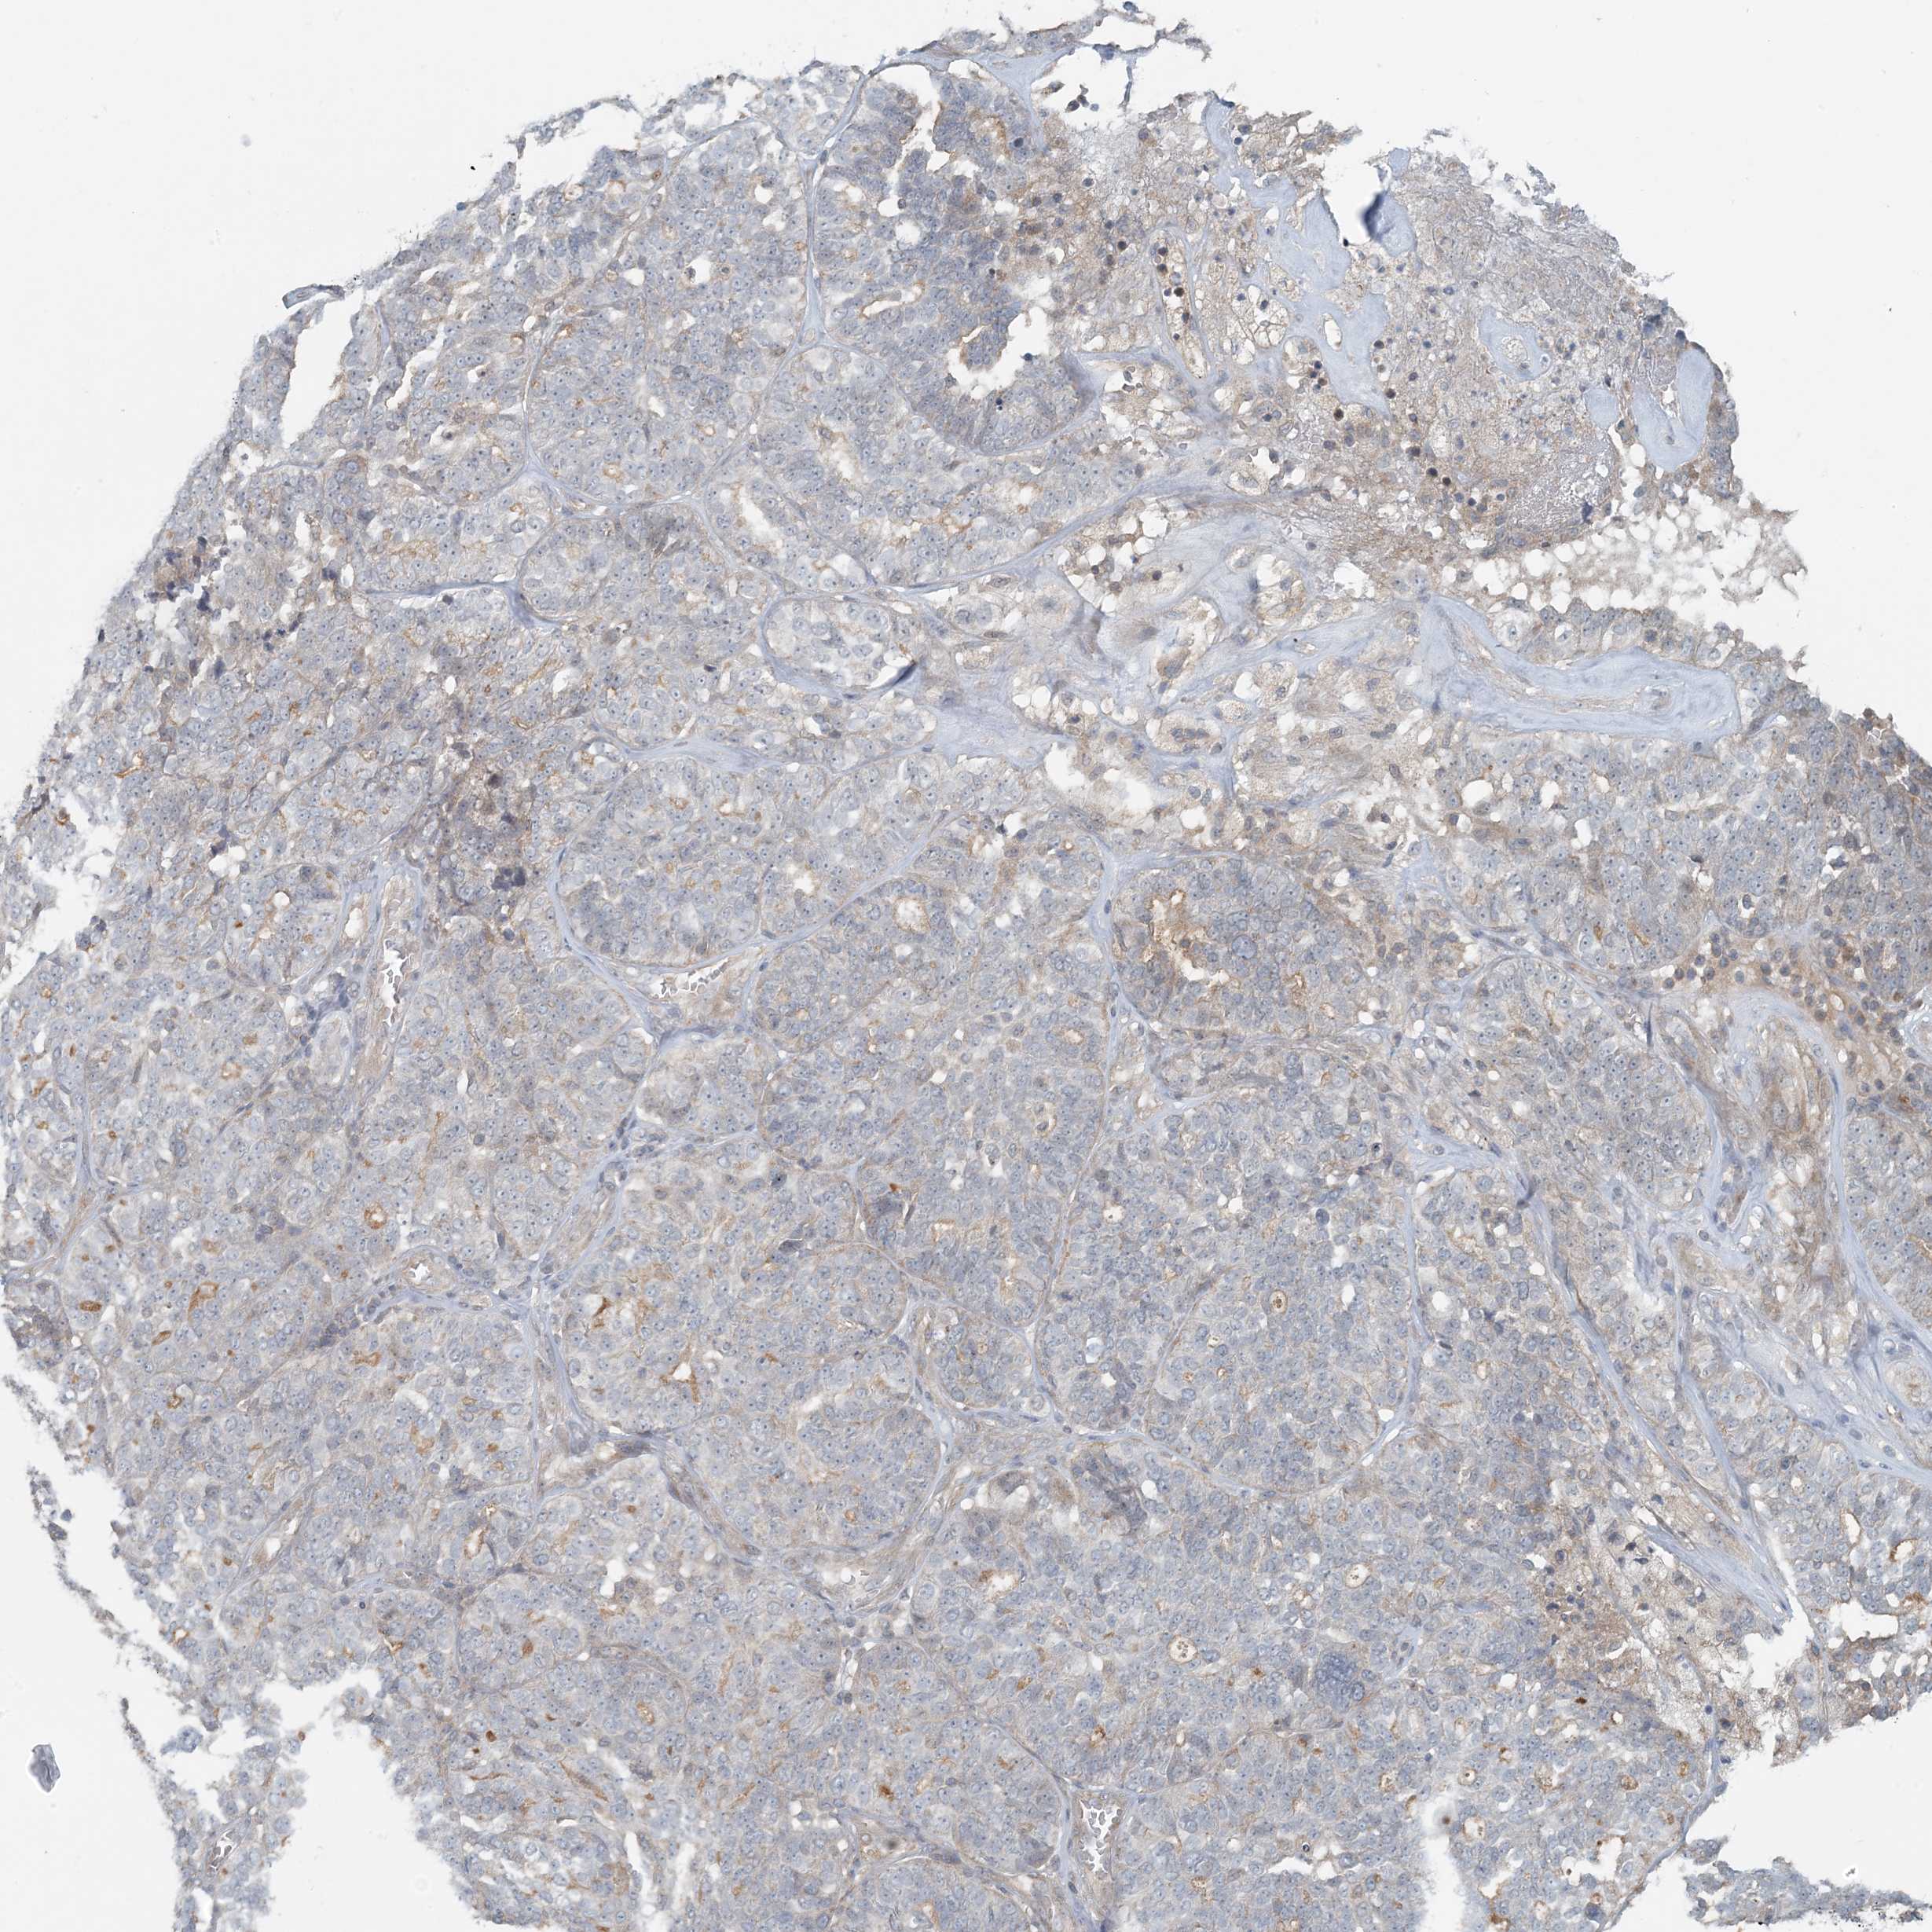

OVARIAN CANCER - Protein expressioni

A mouse-over function shows sample information and annotation data. Click on an image to view it in a full screen mode. Samples can be filtered based on level of antibody staining by selecting one or several of the following categories: high, medium, low and not detected. The assay and annotation is described here.

Note that samples used for immunohistochemistry by the Human Protein Atlas do not correspond to samples in the TCGA dataset.

Antibody stainingi

Antibody staining in the annotated cell types in the current human tissue is reported as not detected, low, medium, or high, based on conventional immunohistochemistry profiling in selected tissues. This score is based on the combination of the staining intensity and fraction of stained cells.

Each image is clickable and will lead to virtual microscopy that enables deeper exploration of all samples and also displays staining intensity scores, fraction scores and subcellular localization as well as patient and tissue information for each sample.

Antibody HPA034785

Antibody HPA034786

Staining

High

Medium

Low

Not detected

Intensity

Strong

Moderate

Weak

Negative

Quantity

>75%

75%-25%

<25%

None

Location

Nuclear

Cytoplasmic/membranous

Cytoplasmic/membranous,nuclear

Carcinoma, endometroid